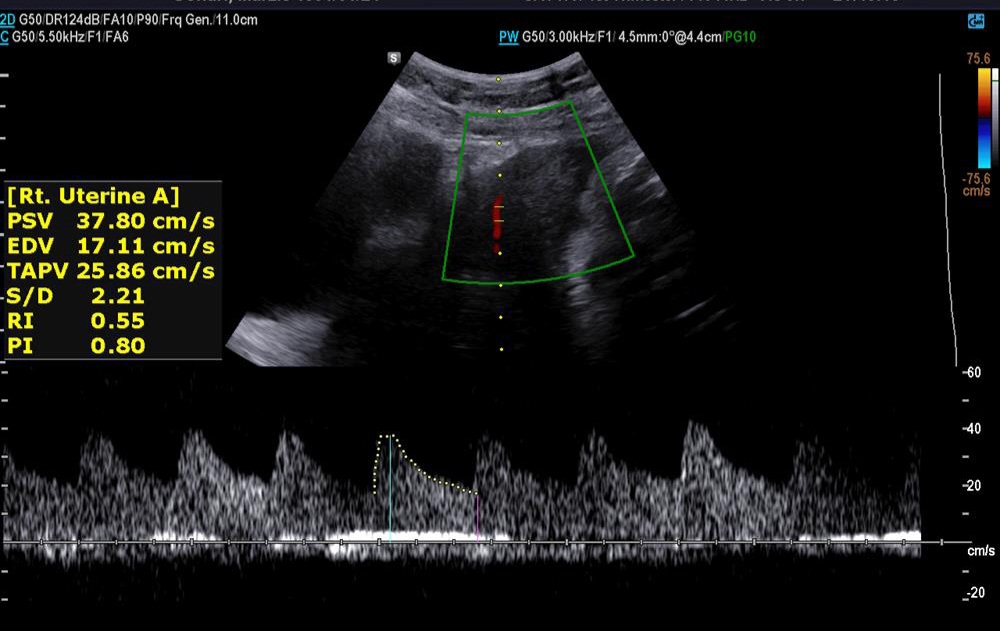

✅️✅️✅️تفسیر سونو داپلر۳۶ هفته🙏🏻

خداروشکر شواهد رشدی بهتر شده و در سونوگرافی شواهدی به نفع محدودیت رشد داخل رحمی و همچنین کمبود اکسیژن جنین وجود ندارد ولی مقداری مقاومت شریانی دارید به پزشکتان حتما مراجعه کنید تا درمورد زایمان و یا شروع انوکساپارین تصمیم گیری شود

جانم pi 2.4 ولی تحت نظر باشید مشکلی ندارد